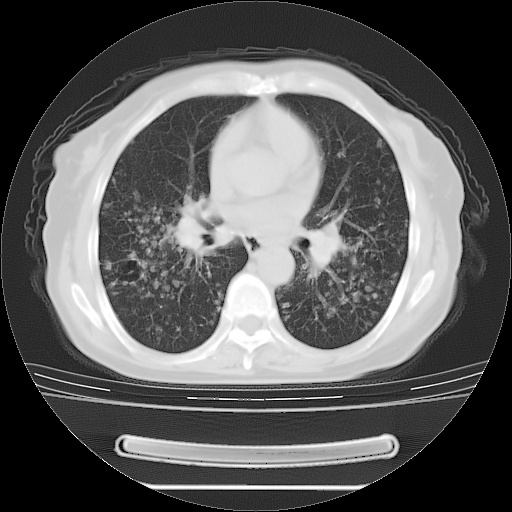

ct示两肺粟粒状病灶,以两肺上叶尖后段及下叶背段分布为主;首先考虑结核。请战友们分析。

考虑 1 弥漫性泛细支气管炎, 2 结核不除外/.  有小叶中心结节 和 树芽征!!

两肺内病灶呈小结节状和树芽状,纵膈的肿大的淋巴结密度不均匀,并见有钙化,考虑为两肺结核可能更大些。

两肺内病灶呈小结节状和树芽状,纵膈的肿大的淋巴结密度不均匀,并见有钙化,多形态病灶,考虑为两肺结核,肝内考虑小囊肿。

病灶以结节为主,大部分边界清楚,分布不均,病灶形态较单一,偶见空泡征,纵膈淋巴结肿大钙化,无结核中毒症状考虑 感染性病变【真菌类可能性大】,细支气管肺泡癌。其他待排

纵隔见肿大淋巴结并钙化,首先考虑结核,但感觉小结节像“挂果”征,分布位于支气管边缘,所以不排外肺泡癌,建议抗唠后复查吧?不然是癌的话,也不好治吧?化疗?